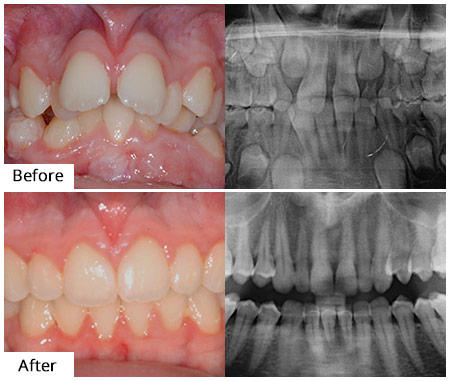

The Best Dentist in Brooklyn Considered as one of the finest dentist available in Brooklyn - and honored as the top New York dentist of 2017 - Family Cosmetic & Implant Dentistry of Brooklyn offers all the most popular dental procedures, from teeth whitening and cleaning to the treatment of complicated issues that require surgery. Both dentists are highly trained and experienced in cosmetic dentistry, as well as general family dentistry. Whatever your dental needs are, they can help. If you’re looking for a cosmetic or family dentist in Brooklyn, who will be capable of treating most dental conditions, look no further. Whether you need cosmetic dentistry, orthodontics or periodontics, the father-and-son, board certified dentists at Family Cosmetic & Implant Dentistry of Brooklyn, will ensure you are confident and comfortable while they treat your oral health and preserve your beautiful smile. Not only can you trust them with your teeth, but your children’s teeth as well. Cosmetic, Family & General Procedures Dr. Alex Khabensky, DDS, and Dr. Igor Khabensky, DDS, are general dentists who also specialize in cosmetic procedures such as veneers, dental implants, and dental crowns just to name a few. Regardless of what procedure you may require, we can do it all. Your oral health is our biggest priority. Which means that before starting any cosmetic procedures, we will first examine your dental health, to lay a stronger foundation for a beautiful smile. Cutting Edge Cosmetic Dental Clinic in Brooklyn Our Brooklyn, dental clinic is equipped with the most state of the art, advanced equipment available anywhere. We have the latest lasers and high precision microscopes. Implant dentists Alexander and Igor Khabensky DDS always use only top quality medical grade titanium or titanium alloy for all our dental implants. We have established relations with the best dental laboratories available in Brooklyn, which enable us to give you the most accurate and natural looking results. Get your dental implant treatments from us, the best implant dentist in Brooklyn. Only board certified and highly trained cosmetic dentist like Alexander or Igor Khabensky DDS can determine an accurate diagnosis and administer the proper dental treatment needed. For more information about the dental services offered at Family Cosmetic & Implant Dentistry of Brooklyn or to schedule a consultation with the top rated dentists, please contact our Brooklyn NY office. For more information about the Family Cosmetic & Implant Dentistry of Brooklyn, please contact our office by number 718-339-8852 Google maps: https://www.google.com/maps?cid=15368240831058200806 https://plus.codes/87G8J25V+C8 Brooklyn Nearby Locations: Midwood, Marine Park, Madison, Homecrest, Mapleton 11204, 11229, 11230, 11234 Family Cosmetic & Implant Dentistry of Brooklyn 2148 Ocean Ave, Ste 401, Brooklyn, NY 11229 718-339-8852 https://www.dentistinbrooklyn.com/ Driving Directions To The Family Cosmetic & Implant Dentistry of Brooklyn: from Brooklyn: https://maps.app.goo.gl/mBFVM4WW9hyQ13Cy5 from Manhattan: https://maps.app.goo.gl/YEH6sFuM5ZKu7y738 from Queens: https://maps.app.goo.gl/vZqa9gqXmbVPzjbG6 from Staten Island: https://maps.app.goo.gl/r1kRiz4r6xEY1KWH8 from Bayonne: https://maps.app.goo.gl/N1gjKSRFxUmEtew1A